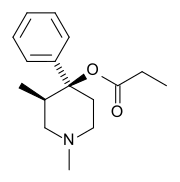

The pharmacodynamic response to an opioid depends upon the receptor to which it binds, its affinity for that receptor, and whether the opioid is an agonist or an antagonist. For example, the supraspinal analgesic properties of the opioid agonist morphine are mediated by activation of the μ1 receptor; respiratory depression and physical dependence by the μ2 receptor; and sedation and spinal analgesia by the κ receptor. Each group of opioid receptors elicits a distinct set of neurological responses, with the receptor subtypes (such as μ1 and μ2 for example) providing even more [measurably] specific responses. Unique to each opioid is its distinct binding affinity to the various classes of opioid receptors (e.g. the μ, κ, and δ opioid receptors are activated at different magnitudes according to the specific receptor binding affinities of the opioid). For example, the opiate alkaloid morphine exhibits high-affinity binding to the μ-opioid receptor, while ketazocine exhibits high affinity to ĸ receptors. It is this combinatorial mechanism that allows for such a wide class of opioids and molecular designs to exist, each with its own unique effect profile. Their individual molecular structure is also responsible for their different duration of action, whereby metabolic breakdown (such as N-dealkylation) is responsible for opioid metabolism.

Phenylpiperidines

- Pethidine (meperidine)

- Ketobemidone

- MPPP

- Allylprodine

- Prodine

- PEPAP

- Promedol